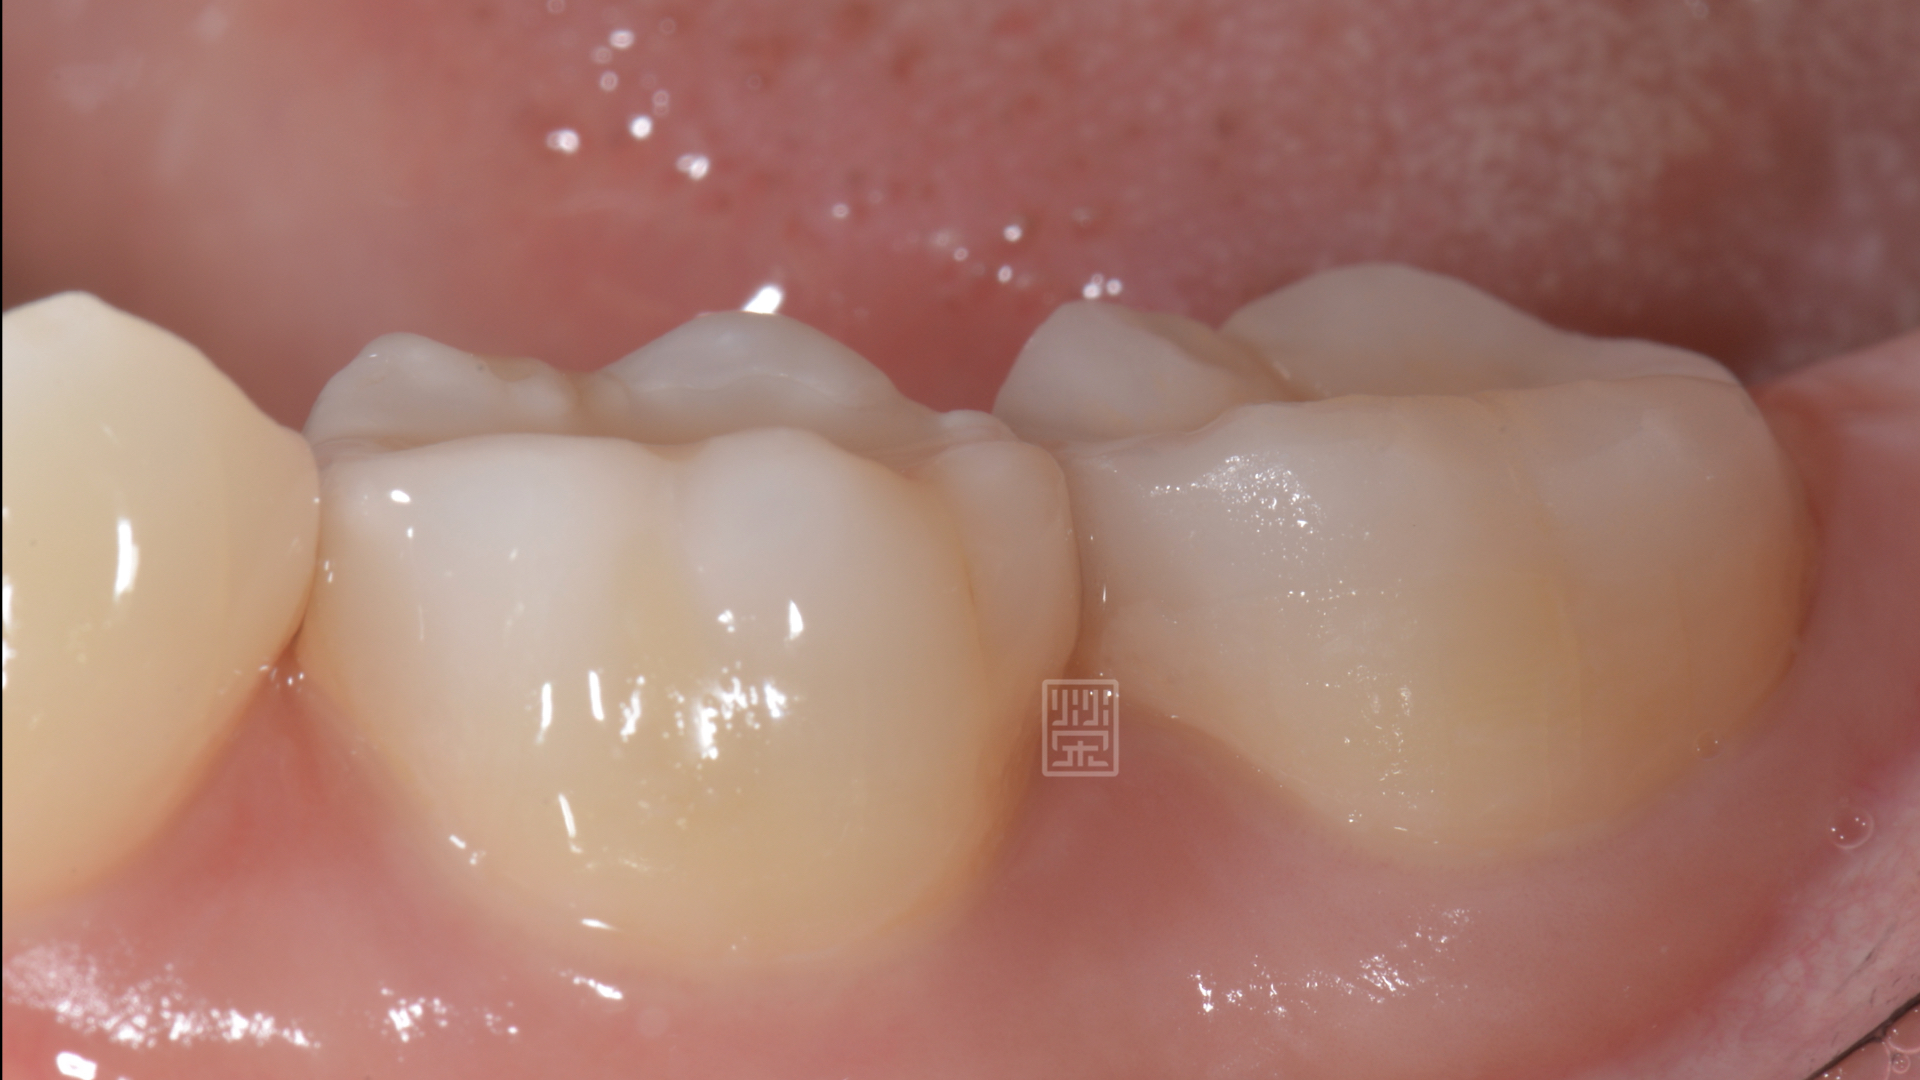

大臼齒整個被磨的凹下去